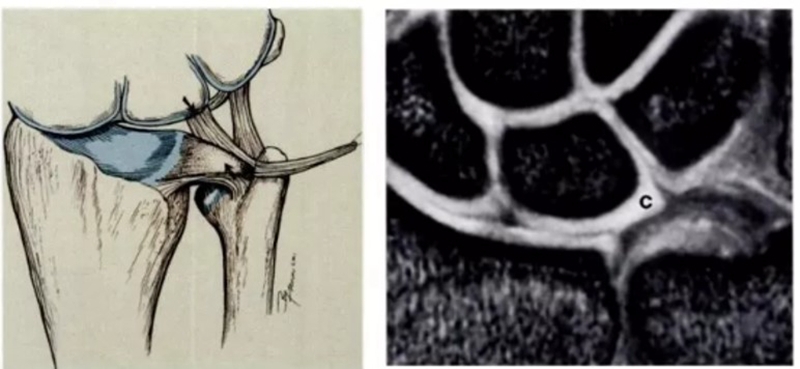

ⅠD,TFC桡侧撕裂,桡侧附着处及桡尺关节处信号增高